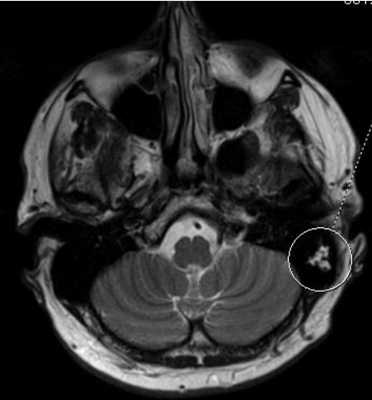

МРТ головного мозга. В аксиальной плоскости отмечается повышение интенсивности МР-сигнала в области ячеек сосцевидного отростка левой височной кости (круг) вследствие ранее перенесенных воспалительных изменений.